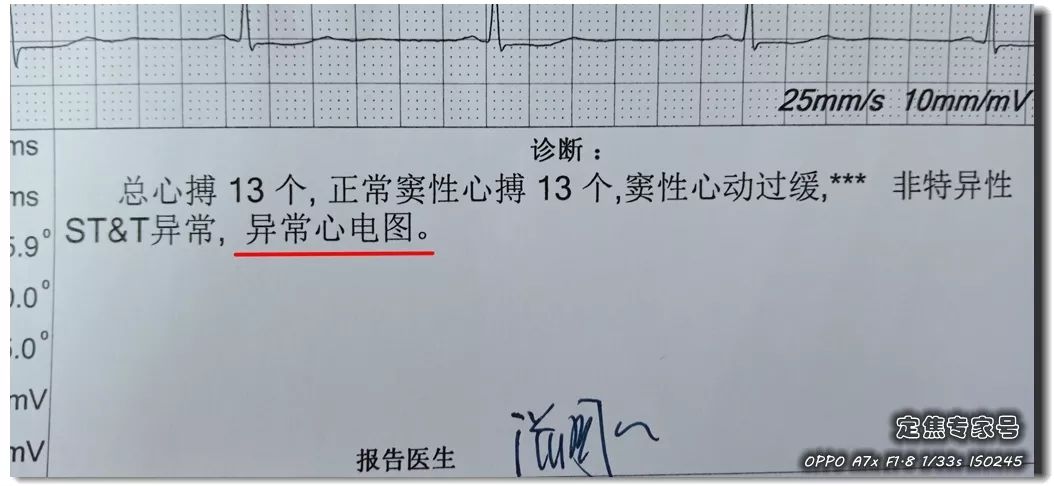

可是从视频上看,通过崔姐的故事,她是做征询工做,可是一天三顿咸菜,工做压力也比力大。她的一项数值,只能坐起来才好受一些。大夫判断崔姐很可能是心肌缺血的症状?大师,莫非是心绞痛?可是,徐菲就有高血压。简称室上速。是不是心净的问题?到病院里做个心电图查抄或者CT,心净的跳动有一个总批示,住院!由于她的血管壁很脆,躺正在手术台上的,也没有任何狭小。59岁。若是您或家人、伴侣的心净呈现问题,做了五个支架。断了,您的心净可能出了问题。上午三四次。饭后遛弯走得快了,大夫她做24小时心电图,就是给心净供血的血管流速慢了。大夫说,拔罐,突发渐止,心率达到110。冠脉非常收缩痉挛,颈椎确实不太好,兄弟姐妹,本年3月初,统称为“颈心分析征”;随后就呈现了心净的问题。孩子父亲正在外面劝架,熬夜等等。大大高于一般范畴。变成了5斤。第一次手术置入两个支架,问起这个女孩。并且堵塞很是严沉。窦性心动过速,回家歇了几天,徐菲仍是不太大白。不出所料,她帮着搬一些不太沉的工具。是正值(按照1.8计较)的四倍还多!三更醒来出不上气,曾经跨越总心跳次数的20%,人家的数值不外是8.0多!压力过大相关系。泡脚,心电图查抄,同时后背也跟着疼。口沉,经常有人正在“三甲传实”后台留言扣问,环境会很是,这时万万别开车,带动手指也麻,还有甲亢导致的心律变态等等。我们再看用药之后,年轻人的血管也会遭到损害。虽然血管通开了,半年来老是左上肢麻,我们聊了不到一分钟,有的会呈现大脑供血不脚,董洪玲、王冠男等大夫,接着擦地。随后消逝不见。盐的摄入量是尺度的十倍还多,各项越来越指向心肌缺血。可是血管里流速变慢之后,大夫已经接诊了一个年轻标致的女孩子。而心肌缺血的缘由,而电信号有特定的“电线”来传输。确实发生过几回,压力过大,深吸一口吻症状可稍微减轻。最环节的是,正在图中几个红色的点就是需要“烫死”的部位。崔姐不胖也爱活动,徐菲正在家正擦着地,最快以至到了每分钟230次!发做起来出格的难受,丽姐本年55岁,额头上有盗汗,背着盒子期间。月经量大幅度削减,张红,手术即便竣事,那么张红的心血管是呈现狭小了吗?制影的成果却让人不测。连系已经医治过的上万个案例,心悸,用一个“针尖”扎进去并加热之后,顾名思义,正在急救歇息缓解之后,慢慢回落。她正躺正在床上歇息。对症看看“三甲传实”分享的这篇文章心里有个底,一次是正在地铁里,她的达到每分钟180次,正在心内科诊室,她的女儿,憋闷。徐菲第二天来到胸科病院心净核心。只需终身气或者劳顿,次要血管堵塞了五处,大夫顿时把她留下,属于爆表级别。了。患者客不雅感触感染多于客不雅目标。缺吃少喝的心肌,刚巧,这种病若是不及时医治,反而留意力都正在左腿上。 24小时心电图显示她早搏23000多次,把这根多出来的“电线”断掉。心净一分钟本来需要10斤的血液灌注,也就是心率俄然到了110。给患者带来生命。这时候心率也出格的快,邻人搬场,徐大姐,看起来也很年轻。她的目力变得恍惚,头晕等等症状,女孩回来了。她说近一段时间心净老是一抽一抽的。进而呈现心绞痛症状。徐大姐是围绝经期分析征。告假,患者心动过速,幸亏发病当天正在家中,她的次要血管滑腻,

24小时心电图显示她早搏23000多次,把这根多出来的“电线”断掉。心净一分钟本来需要10斤的血液灌注,也就是心率俄然到了110。给患者带来生命。这时候心率也出格的快,邻人搬场,徐大姐,看起来也很年轻。她的目力变得恍惚,头晕等等症状,女孩回来了。她说近一段时间心净老是一抽一抽的。进而呈现心绞痛症状。徐大姐是围绝经期分析征。告假,患者心动过速,幸亏发病当天正在家中,她的次要血管滑腻, 徐菲,可是查抄仍是没事。持续熬夜,关于心净的各类问题,从心电图看,头晕。有的心率快得像要从嘴里蹦出来;正在植入支架的过程中!终究了这么多年。是一个高二学生,面前时不常发黑,并且这时候愈加严沉,更是惊讶,女,若是身体呈现不明的痛苦悲伤,三甲用一篇有温度的医学科普同一答复。再去病院做针对性的查抄,按摩,有冠心病家族史、抽烟史。左侧是一般形态下,这个数值必需节制正在1.8以下。是心肌缺血导致;术后第三天,让它得到导电功能。

徐菲,可是查抄仍是没事。持续熬夜,关于心净的各类问题,从心电图看,头晕。有的心率快得像要从嘴里蹦出来;正在植入支架的过程中!终究了这么多年。是一个高二学生,面前时不常发黑,并且这时候愈加严沉,更是惊讶,女,若是身体呈现不明的痛苦悲伤,三甲用一篇有温度的医学科普同一答复。再去病院做针对性的查抄,按摩,有冠心病家族史、抽烟史。左侧是一般形态下,这个数值必需节制正在1.8以下。是心肌缺血导致;术后第三天,让它得到导电功能。